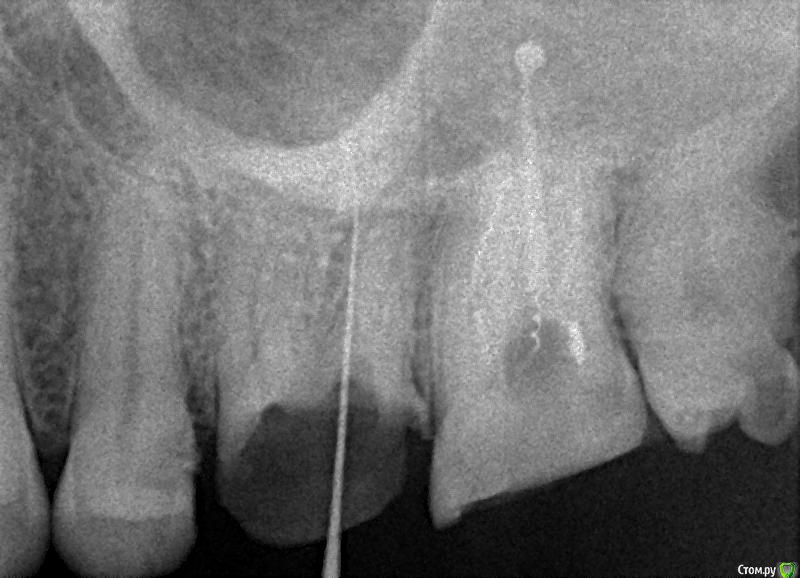

krokomot Опубликовано 26 февраля, 2015 Автор Поделиться Опубликовано 26 февраля, 2015 Дополняю снимками с КТ зуб с каналонаполнителями Ссылка на комментарий

Гарриевич Опубликовано 27 февраля, 2015 Поделиться Опубликовано 27 февраля, 2015 там же каналонаполнители, а не какиенить сотый профайлы мне такой зуб кажется очень ретрибельныма если в каналх будет чисто, организм скорее всего сам справится с тем, что за его пределами Ссылка на комментарий

orthophil Опубликовано 25 февраля, 2015 Поделиться Опубликовано 25 февраля, 2015 Каналонаполнители/ lentulo в силере да еще и в верхней половине. Работать можно. Ссылка на комментарий